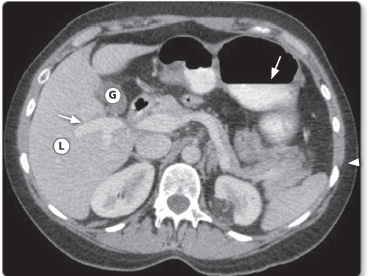

Figure 1.17: CT image of the abdomen showing different contrast densities and accurate anatomical delineation of abdominal organs. L = Liver; G= Gallbladder. Iodinated contrast in the portal vein and in stomach (arrows).